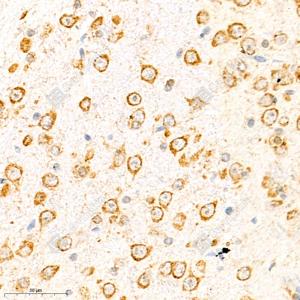

IHC检测Neuropilin 1蛋白(货号 GB111325). 样品: 小鼠脑, 4%多聚甲醛 (货号G1101) 固定12-24小时. 抗原修复: 柠檬酸抗原修复液(干粉, pH 6.0) (G1201), 98℃, 20分钟. —抗: 1: 1400稀释, 4℃ 孵育过夜. 二抗: HRP标记山羊抗兔IgG (H+L) (货号GB23303), 1: 200稀释, 室温孵育1小时. |

IHC检测Neuropilin 1蛋白(货号 GB111325). 样品: 大鼠脑, 4%多聚甲醛 (货号G1101) 固定12-24小时. 抗原修复: 柠檬酸抗原修复液(干粉, pH 6.0) (G1201), 98℃, 20分钟. —抗: 1: 1400稀释, 4℃ 孵育过夜. 二抗: HRP标记山羊抗兔IgG (H+L) (货号GB23303), 1: 200稀释, 室温孵育1小时. |